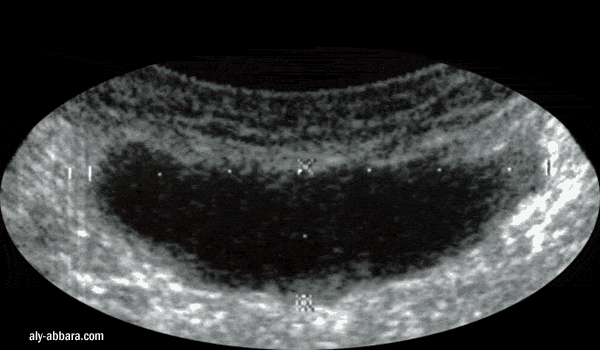

Aspect échographique d'une collection sérosanglante (une sérocèle) au niveau du plan sous cutané

d'une cicatrice de césarienne (par incision transversale de Pfannenstiel) 16 jours auparavant.